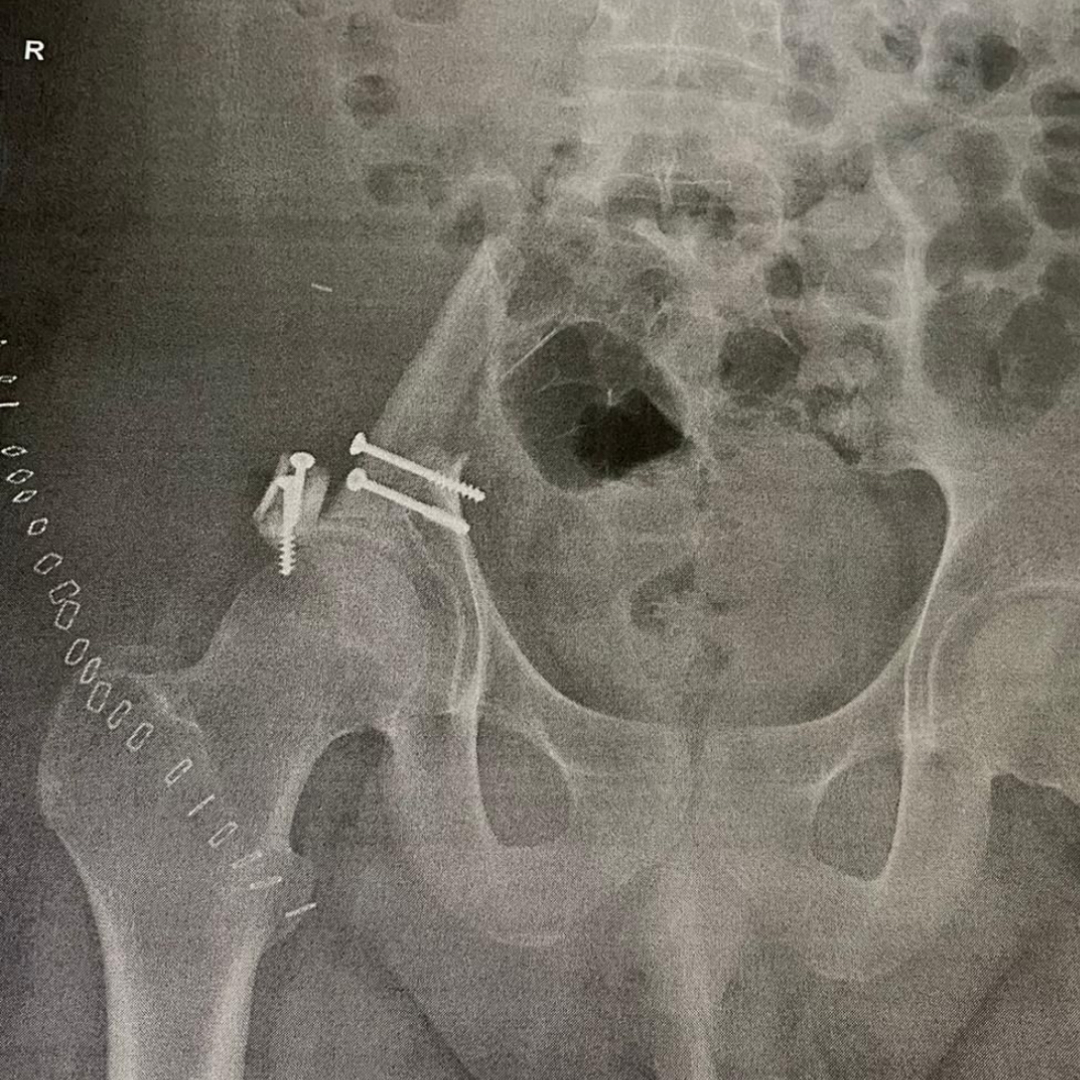

Ende Oktober wurden die Schmerzen deutlich schlimmer, und ich sagte endlich etwas. Wir fuhren direkt in die Notaufnahme, und zwei Tage später wurde ein MRT gemacht. Der Verdacht war ein Ewing- oder Osteosarkom. Am selben Tag mussten wir noch ins Sarkomzentrum nach Berlin-Buch fahren. Dort wurden eine Biopsie, ein PET-CT und viele andere Untersuchungen gemacht. Die Diagnose lautete: Ewing-Sarkom in der rechten Beckenschaufel, etwa 16 × 10 × 12 cm groß.

Am 27.07.2021 war dann die OP. Es wurde die gesamte rechte Beckenschaufel bis zum Kreuzbein und zur Hüfte entfernt, samt Beckenring, und dafür das Wadenbein eingesetzt. Die OP dauerte etwa fünf Stunden. Danach hatte ich eine Woche Bettruhe. Den Rest der Therapiezeit war ich im Rollstuhl und auf Krücken unterwegs, denn mein rechtes Bein durfte ich über ein halbes Jahr lang nicht belasten. Nach der OP folgten noch zwei VAI-Chemos, und im September kam dann die Hochdosis-Chemotherapie mit Transplantation meiner eigenen Stammzellen (die hatte ich bereits im Februar gesammelt). Ich war drei Wochen in Isolation – aber meine Mama durfte trotzdem zu mir. Sie war an meiner Seite, und wir sind ein unschlagbares Team. Sie hat mir sehr geholfen, alles zu schaffen, und war immer für mich da. Die Hochdosis-Chemo war gleichzeitig der Abschluss der Therapie.